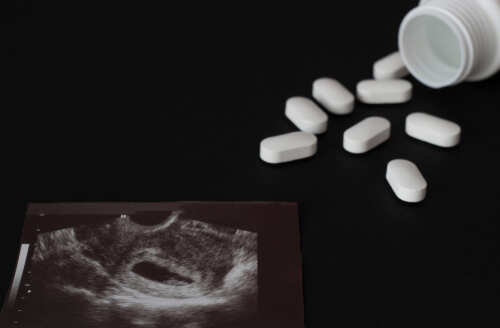

On September 3, 2025, the Texas Senate passed House Bill 7, marking a decisive escalation in the state’s effort to restrict abortion access. This legislation gives private citizens the right to sue anyone manufacturing, prescribing, distributing, or mailing abortion pills to or from Texas—targeting out-of-state providers and shipping firms. With damages set at a minimum of $100,000 per violation, the bill is a direct response to the growing prevalence of medication abortions, which now account for nearly two-thirds of all abortion procedures nationwide. The move comes as Attorney General Ken Paxton aggressively enforces existing bans, issuing cease-and-desist orders to organizations and individuals shipping abortion pills into Texas.